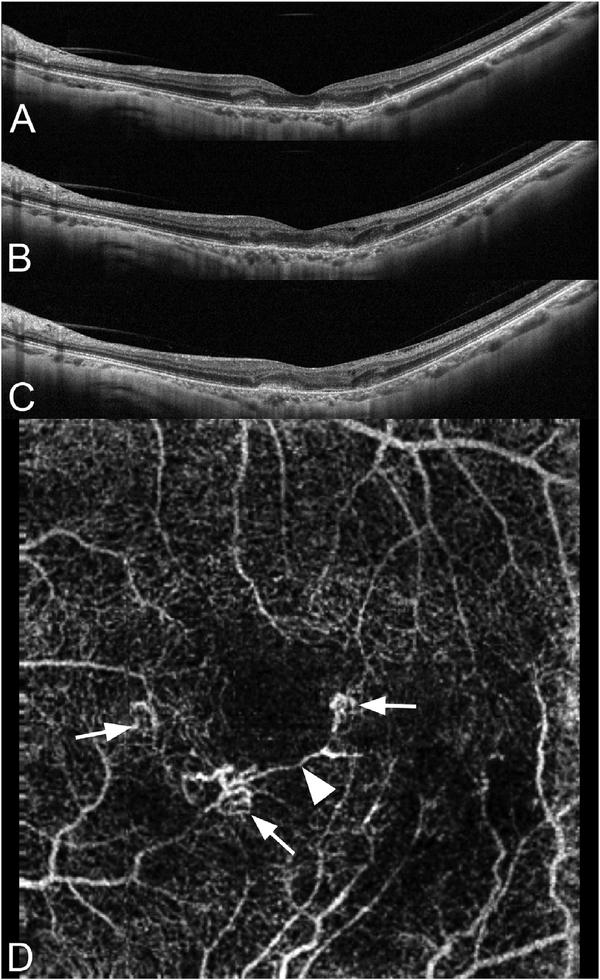

Optical coherence tomography (OCT) was one of the biggest advances in ophthalmic imaging. Building on that platform, OCT angiography (OCTA) provides depth resolved images of blood flow in the retina and choroid with levels of detail far exceeding that obtained with older forms of imaging. This new modality is challenging because of the need for new equipment and processing techniques, current limitations of imaging capability, and rapid advancements in both imaging and in our understanding of the imaging and applicable pathophysiology of the retina and choroid. These factors lead to a steep learning curve, even for those with a working understanding dye-based ocular angiography. All for a method of imaging that is a little more than 10 years old. This review begins with a historical account of the development of OCTA, and the methods used in OCTA, including signal processing, image generation, and display techniques. This forms the basis to understand what OCTA images show as well as how image artifacts arise. The anatomy and imaging of specific vascular layers of the eye are reviewed. The integration of OCTA in multimodal imaging in the evaluation of retinal vascular occlusive diseases, diabetic retinopathy, uveitis, inherited diseases, age-related macular degeneration, and disorders of the optic nerve is presented. OCTA is an exciting, disruptive technology. Its use is rapidly expanding in clinical practice as well as for research into the pathophysiology of diseases of the posterior pole.

光学相干断层扫描(OCT)是眼科成像领域的重大突破之一。在此基础上,OCT 血管造影术(OCTA)提供了视网膜和脉络膜血流的深度分辨图像,其细节水平远远超过了旧的成像方式。这种新的模式具有挑战性,因为需要新的设备和处理技术,目前成像能力的限制,以及成像和对视网膜和脉络膜成像及适用病理生理学的理解的快速发展。这些因素导致学习曲线陡峭,即使对于那些对基于染料的眼部血管造影术有一定了解的人来说也是如此。所有这些都是为了一种成像方法,它的历史还不到 10 年。这篇综述从 OCTA 的发展历史和 OCTA 中使用的方法开始,包括信号处理、图像生成和显示技术。这是理解 OCTA 图像显示内容以及图像伪影产生原因的基础。本文还回顾了眼部特定血管层的解剖结构和成像。介绍了 OCTA 在评估视网膜血管阻塞性疾病、糖尿病性视网膜病变、葡萄膜炎、遗传性疾病、年龄相关性黄斑变性和视神经疾病的多模态成像中的整合。OCTA 是一种令人兴奋的、颠覆性的技术。它在临床实践中的应用以及对后极部疾病病理生理学的研究中迅速扩展。